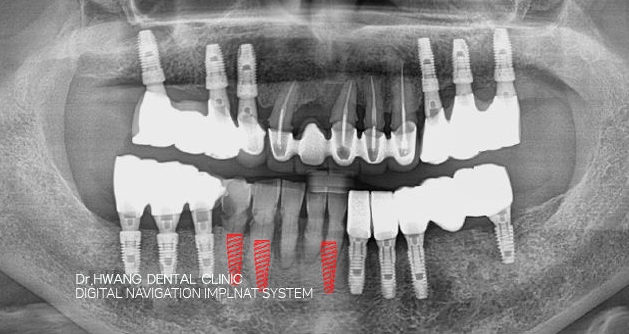

재수술 임플란트

가능하면 뼈이식만으로 기존 임플란트를 살리려 합니다.

무조건 기존 임플란트를 제거하기 보다 잇몸염증 치료 후

가능한 잇몸뼈 이식 만으로 기존 임플란트를 살리려

노력합니다.

실패한 임플란트가 제 기능을 할 수 있도록 임플란트를

복원 또는 재식립하는 치료

닥터황치과 원장은 문제가 되는 임플란트에 대하여 풍부한

경험과 치료에 대한 노하우를 가지고 있습니다.